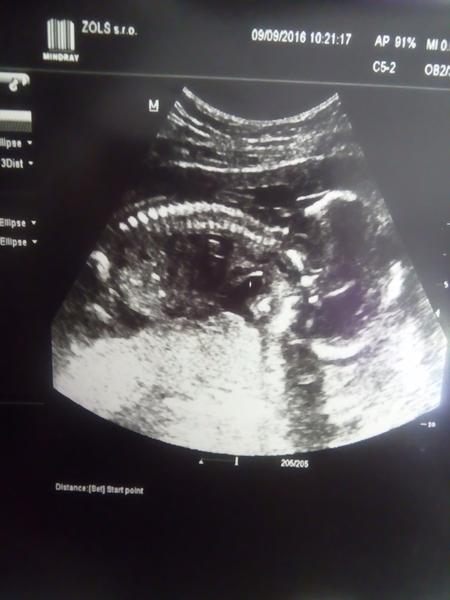

No my mame velkeho tajnostkara 🙂 neukazal sa nam,ach..8tyzdnov som na to cakala a nevieme co cakame,hlavne ze je v poriadku. Len sa mi zda nejake mrňaté,lebo ze len okolo 280g ma a je tak cudne otocene,ze chrbatik nema dole ale hore,takze je tvarou dole :D no nechapem jak sa to dalo škvrňa 🙂

Nepridalo foto,tak pridavam